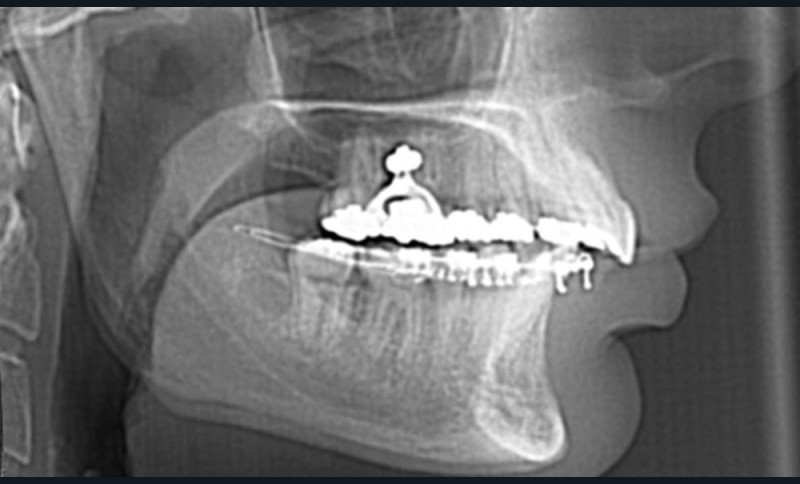

Le Dr Christophe Dunglas développera ensuite l’intérêt du cone beam lors de la mise en place des canines incluses difficiles. En effet, la préparation d’ancrages adéquats et de gestes chirurgicaux a minima préviendra l’apparition de résorptions radiculaires et de lésions parodontales.